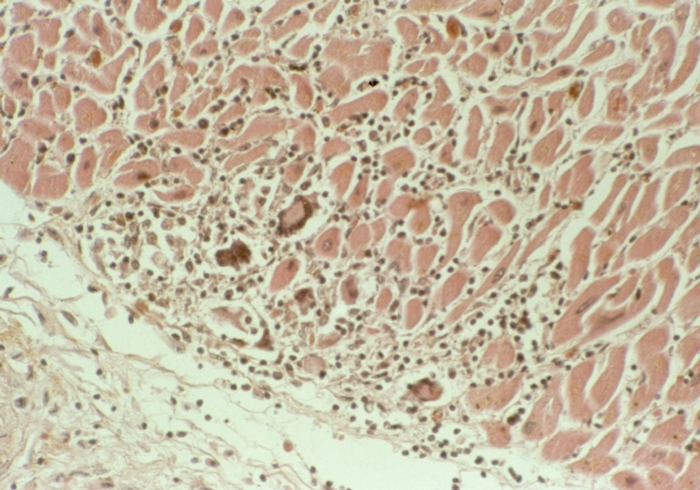

Межуточный миокардит: гистологические исследования